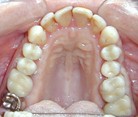

Electrogalvanismo por

presencia de amalgamas en el maxilar superior e inferior